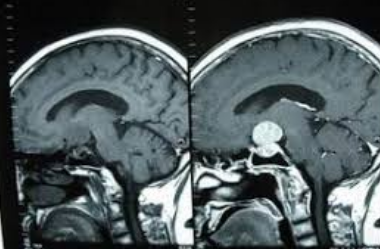

生长激素型垂体瘤一线治疗是神经内镜手术经蝶窦手术;其手术效果好,创伤小,顺利性增加,是患者治疗的较好的选择!相比显微镜手术,神经内镜可提供范围更广、照明更佳的术野,解决显微镜手术盲区的问题;同时神经内镜的多角度变化可在切除肿瘤的同时减少并发症的发生,且不需损害鼻腔的正常结构,是目前众多垂体瘤患者青睐的手术。

很多时候,神经内镜手术需要配合放疗、药物等辅助治疗。这是由于生长激素型垂体瘤与库欣病不同的是,产生gh的肿瘤通常很大,而且是局部侵袭性的。对于小的、边界清楚的肿瘤,神经内镜手术经蝶窦手术可能是合适的,而对于较大的、局部侵袭性的肿瘤,手术可能有利于肿瘤的减压,但持续性或复发性疾病是常见的,需要辅助治疗。无论是原发放疗还是手术后放疗,治疗效果起效缓慢,与治疗相关的全垂体功能低下发病率高。